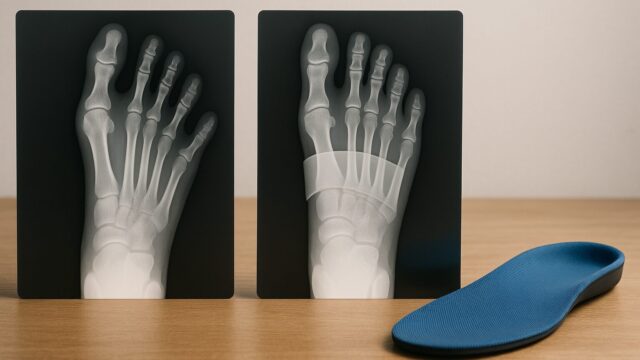

5. 浮き指改善インソールの活用術と靴との相性

スニーカーだけでなく、インソール(中敷き)を活用することも浮き指の負担軽減や改善サポートに役立ちます。特に「横アーチ」をサポートするパッド(中足骨パッド)が付いたインソールは、潰れてしまったアーチを持ち上げ、自然と指が地面に下りるように誘導してくれます。

ただし、インソールを入れる際は、元々入っている中敷きが取り外せるタイプのスニーカーを選ぶことが重要です。取り外せないタイプの上に重ねて入れると、靴の中が窮屈になり、かえって指を圧迫してしまう恐れがあります。ニューバランスなどの機能性スニーカーは、カップインソール(取り外し可能)になっているものが多く、市販の矯正インソールとの相性も抜群です。靴とインソールの合わせ技で、より効果的な改善を目指しましょう。